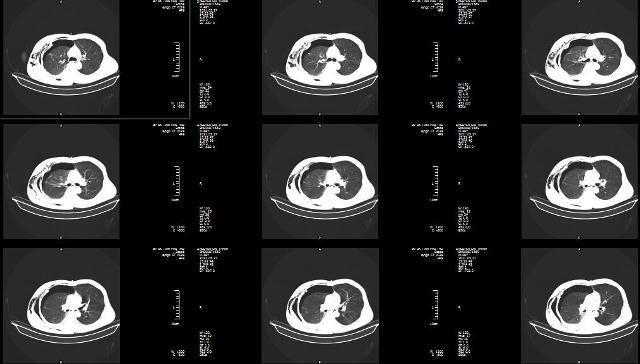

Người bệnh là Nguyễn Chí Th (sinh năm 1972) ở xã Đồng Lương - huyện Cẩm Khê - tỉnh Phú Thọ được đưa vào Bệnh viện đa khoa tỉnh Phú Thọ trong tình trạng kích thích, mạch nhanh, huyết áp không đo được. Anh bị băng tải dây chuyền cuốn vào nên cụt toàn bộ cánh tay phải, dập nát nhiều, lộ xương đầu cánh tay, tràn khí dưới da thành ngực phải.

Người bệnh được đặt ống nội khí quản, sơ cứu ban đầu và được chỉ định chụp chiếu. Kết quả chụp cho thấy người bệnh bị gãy toàn bộ xương sườn ở bên phải gây tràn dịch, tràn khí màng phổi, tràn khí trung thất, đụng dập nhu mô phổi. Các chuyên khoa đã nhanh chóng hội chẩn và người bệnh được chỉ định cấp cứu: Mở màng phổi, dẫn lưu khí máy màng phổi và tạo mỏm cụt tay phải.

Sau phẫu thuật, người bệnh được chuyển về Khoa Hồi sức tích cực - Chống độc trong tình trạng nặng nề, hôn mê, thở máy, sốc đa chấn thương nặng. Các bác sĩ trong Khoa đã điều trị tích cực cho người bệnh bằng nhiều biện pháp: Thở máy, duy trì hút dẫn lưu màng phổi liên tục, nội soi phế quản tại giường, dùng kháng sinh.

Sau bảy ngày điều trị, tình trạng của người bệnh có nhiều tiến triển, đã cai được máy thở, rút ống nội khí quản, rút dẫn lưu màng phổi, đáp ứng tốt với điều trị. Hiện tại người bệnh đã tỉnh táo, tự thở tốt và được chuyển lên Đơn vị Phẫu thuật Tim mạch - lồng ngực để xử lý ổ cặn, dày dính màng phổi và xương sườn gãy.